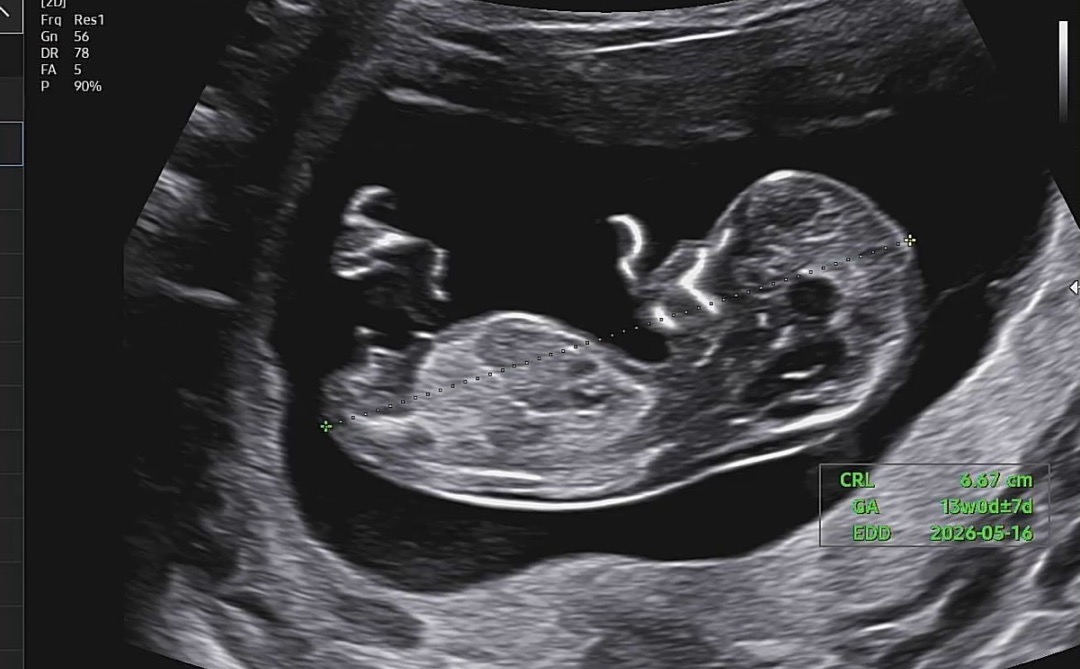

오늘 첫 기형아 검사 하고 왔어요!! 각도법 한번 봐주세용😇🫶🏻🫶🏻🫶🏻